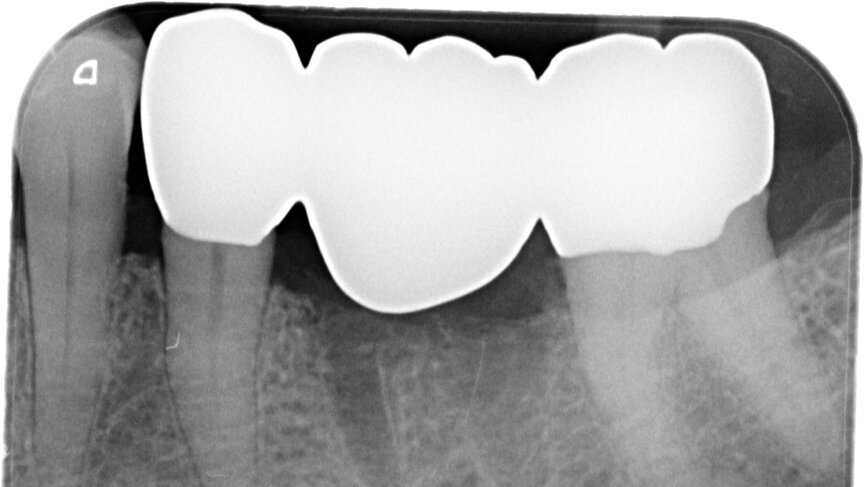

Fig. 13: Final radiograph used to check for excess cement around the bridge.